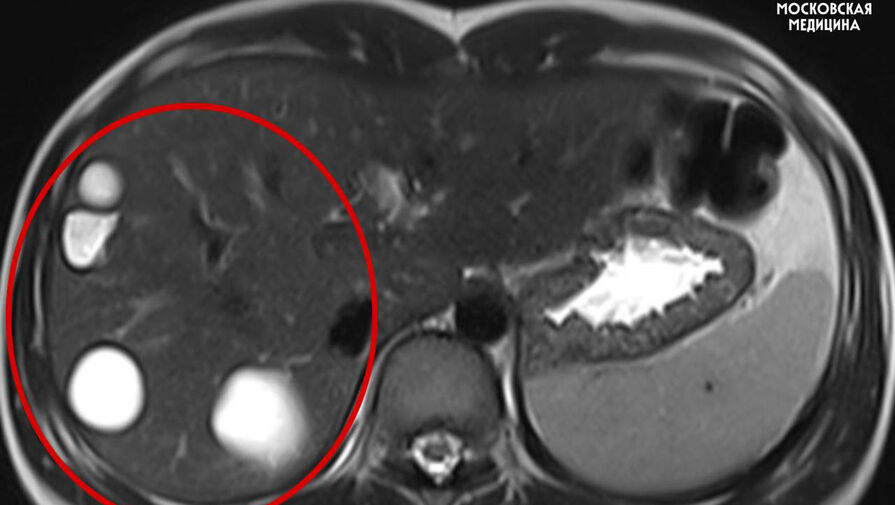

Врачи больницы имени Сперанского спасли 14-летнюю девочку с множеством паразитарных кист в печени. Об этом сообщили в пресс-службе столичного департамента здравоохранения.

Кисты медики обнаружили случайно во время планового обследования. После этого ребенка направили на операцию.

Во время вмешательства специалисты удалили пять кист с использованием лапароскопии. Через пять дней после операции пациентку выписали домой.